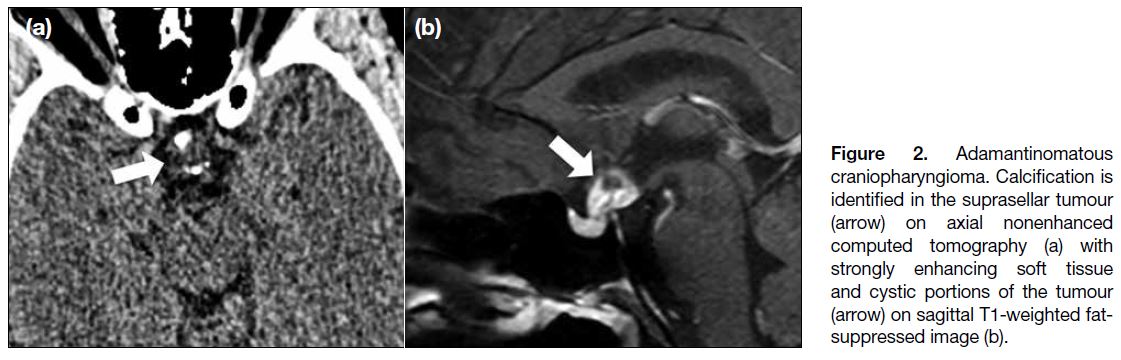

Approximately 1.2% to 4.0% of paediatric brain

tumours are craniopharyngiomas, which are commonly

located in the sellar and suprasellar regions.[5] The adamantinomatous type is more common in childhood.

Imaging features include calcifications and cystic

components, which are found in our case (Figure 2).

Figure 2. Adamantinomatous

craniopharyngioma. Calcification is

identified in the suprasellar tumour

(arrow) on axial nonenhanced computed tomography (a) with strongly enhancing soft tissue and cystic portions of the tumour (arrow) on sagittal T1-weighted fat-suppressed image (b).